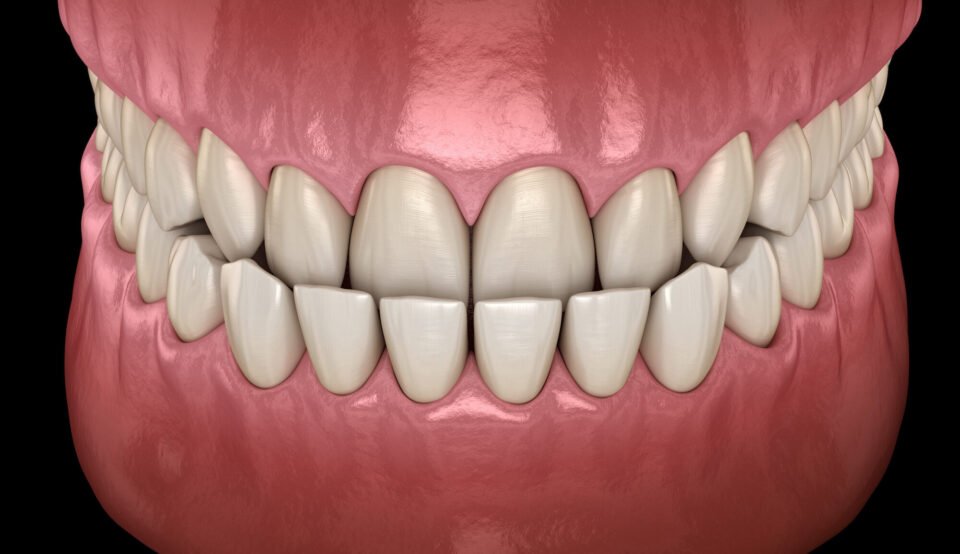

Przodozgryz (zgryz III klasy, Klasa III) to wada, w której dolne siekacze stoją z przodu względem górnych przy zamkniętych zębach. W prawidłowym zgryzie górne zęby przednie powinny lekko zachodzić na dolne od zewnętrznej strony. Przy przodozgryzie relacja jest odwrócona: dolne siekacze są z przodu, górne za nimi lub stykają się krawędziami.

Odróżniamy dwa typy tej wady. Przodozgryz zębowy oznacza, że szczęki są ustawione prawidłowo, ale same zęby wychylone w nieprawidłowych kierunkach – górne siekacze cofnięte do wewnątrz, dolne wychylone do przodu. Przodozgryz szkieletowy to wada proporcji kości: zbyt mała lub cofnięta górna szczęka, zbyt duża lub wysunięta żuchwa, lub oba elementy razem. Szkieletowy typ daje charakterystyczny profil z cofniętą środkową częścią twarzy i wysuniętą brodą.

- Przodozgryz zębowy – górne siekacze cofnięte do wewnątrz, dolne wychylone do przodu; szczęki ustawione prawidłowo; korygowany aparatem bez operacji

Przy zamkniętych zębach dolne zęby przednie są z przodu względem górnych zamiast za nimi. To podstawowy i wyraźny objaw przodozgryzu przedniego.